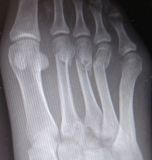

1. Ηallux valgus of the right foot in a 28-year-old female.

Treatment: Scarf osteotomy of the first metatarsal

I. Anteroposterior x-ray foot during procedure shows the scarf osteotomy with two screws II. This image shows the foot in a standing position one year down the line from the procedure. The young lady is very happy.